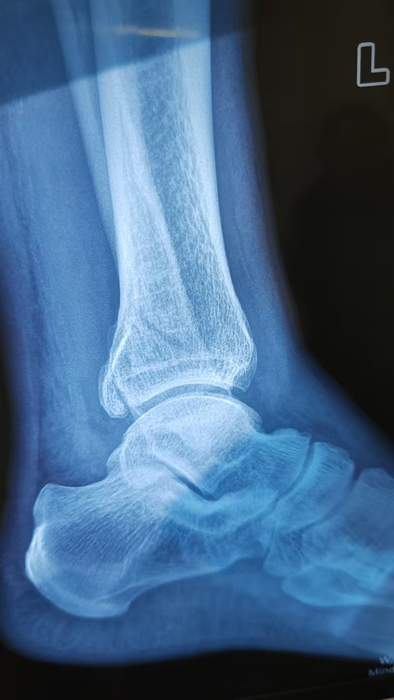

2月4日,何店鎮(zhèn)中心衛(wèi)生院接診一名左踝關(guān)節(jié)外傷患者,經(jīng)影像檢查,確診為左脛、腓骨下段骨折。外科醫(yī)生姜穩(wěn)迅速完成術(shù)前檢查及病情評估,并與患者及家屬深入溝通治療方案。在患者強烈要求于本院進行手術(shù)的情況下,為最大限度保障手術(shù)質(zhì)量與安全,該院特邀請醫(yī)共體牽頭單位——曾都區(qū)人民醫(yī)院脊柱創(chuàng)傷外科專家團隊前來指導(dǎo)。